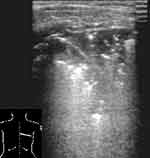

В норме при сканировании датчиком 7,5 МГц последовательно визуализировались следующие структуры: гипоэхогенный слой подкожной жировой клетчатки, тонкая эхогенная полоска наружного листка собственной фасции груди, гипоэхогенные мышечные слои, представленные мышцами плечевого пояса, брюшной стенки и межреберными мышцами с разделяющими их листками фасций. Мышечную ткань нетрудно отличить от жировой клетчатки, даже если полоска фасции отчетливо не видна. Глубже визуализируется эхогенная полоска внутренней грудной фасции, тонкий гипоэхогенный слой рыхлой клетчатки. Затем более тонкая эхогенная полоска, толщиной до 1 мм, являющаяся суммой отражения от париетального, висцерального листков плевры и границы мягкие ткани/воздушная легочная ткань. Просвет между листками плевры не виден. Наружный контур плевры ровный, можно увидеть зазубрину, соответствующую междолевой щели, а внутренняя поверхность эхогенной плевральной полоски не такая четкая и ровная, как наружная. Под ней регистрируются отдельные точечные эхосигналы. При дыхании отчетливо видно скольжение плевральных листков, вместе с висцеральным листком смещаются и точечные эхосигналы. Далее идут постепенно затухающие реверберации отражения от поверхности воздушной легочной ткани (Рис. 1).

[Увеличить]

Рис. 1. Нормальная эхограмма легкого.

Если используется датчик 3,5 МГц можно дифференцировать гипоэхогенную подкожную жировую клетчатку и мышечный слой, затем визуализируется эхогенная полоска плевральных листков и границы воздушной легочной ткани. Ее толщина несколько больше, чем при сканировании датчиком 7,5 МГц и составляет 1-1,5 мм, возможно из-за более глубокого проникновения ультразвуковой волны в воздушную легочную ткань. Во время исследования обращали внимание на положение и подвижность нижних краев легких, их симметричность.